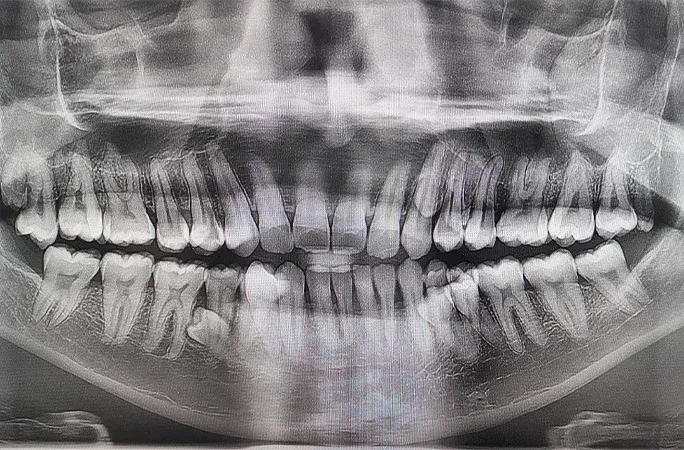

แต่ความพีคยังไม่จบเพียงเท่านี้! ผลการเอกซเรย์โดยทันตแพทย์เผยให้เห็นว่า ยังมีฟันที่ "ซ่อนอยู่" และยังไม่โผล่พ้นเหงือกอีกถึง 4 ซี่ จนกระทั่งต้นปี 2023 ฟันเหล่านั้นก็ได้ปรากฏตัวออกมาครบถ้วน ทำให้เขามีฟันรวมทั้งหมด 42 ซี่ ส่งผลให้เขาได้รับการบันทึกสถิติโลกจาก Guinness World Records ในฐานะ "ผู้ชายที่มีฟันมากที่สุดในโลก" (Most teeth in a person’s mouth - male)